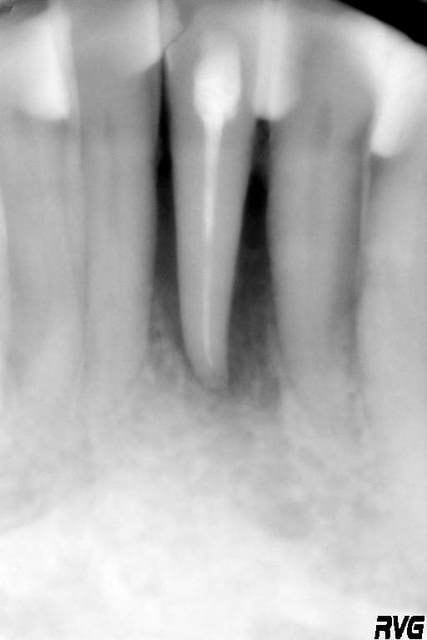

20/09/2005 à 00h00

Oui ça ressemble à un canal latéral non obturé, d'autant que le TR parait étrangement rectiligne, même pour une incisive inf.

La cavité d'accès montre qu'une minéralisation rendait le traitement difficile.

Donc oui, un canal oublié.

Mais je suis tombé dans un piège....non?

c'est pas moi qui est fait l'endo ......d'ac avec toi steph ou ....une petite partie de la table vest a disparu ....par contre le parodonte s'est reformé au dessus